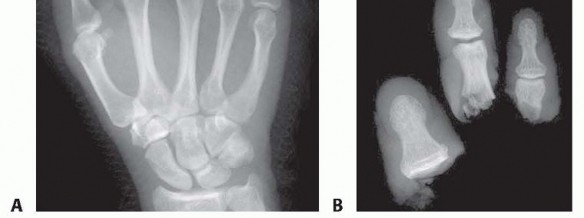

A survival rate greater than 80% is expected for replantation surgery.Functional outcomes are greatest for replantation of the thumb, proximal hand, and single digit distal to the FDS insertion (FIG 6A-D).5,6,13,16Recovery of sensation is correlated with function. As in other peripheral nerve injuries, age is the most important factor for recovery, with better results in younger patients. The average two-point discrimination inreplanted thumbs is 11 mm and in fingers is 8 mm.4 These values represent the average recovery for sharp amputation. Crush and avulsion mechanisms result in poorer two-point discrimination.Range of motion is related to level of amputation. Active PIP joint motion in replantations proximal to the FDS insertion average 35 degrees, whereas replantations distal to the FDS insertion result in 82 degrees of PIPjoint motion (FIG 6E-G).7

FIG 6 • A-D. This patient sustained an amputated thumb, which was successfully replanted with good cosmetic and functional results. E-G. Successful replantation of the ring and small fingers resulted in a functional hand capable of holding common objects. Vigilant reexamination of color, warmth, turgor, and capillary refill is necessary to decide whether exploration in the operating room is indicated. Revisions after 4 to 6 hours of reduced perfusionseldom result in digit salvage.7If venous engorgement occurs postoperatively, elevate the hand and remove constrictive dressings (including sutures that are too tight).Consideration for return to the operating room is based on intraoperative findings affecting the possibility of revising the venous anastomosis.If this is not possible, leeches or nail removal are used to alleviate venous congestion. These methods typically are used to bridge the first 4 to 6 days until adequate outflow is established.